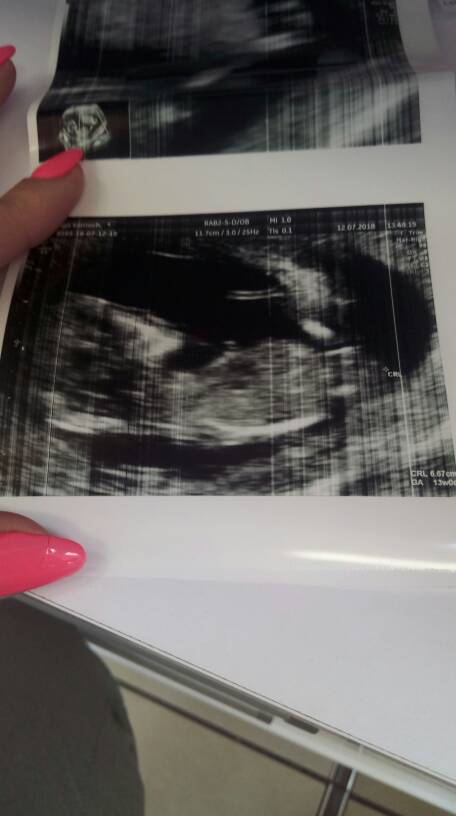

My już po [emoji4] Dzidzia ma 6.7cm [emoji7] jest też łobuziak ruchliwy, ciągle wierga nogami i rękami. Ale udało się pomierzyć wszystko i wszystko jest jak najbardziej w porządku. Doktorek mówi, że wygląda na prawdę na zdrowiutkiego dzidziusia [emoji7] Tak sie ciesze! Serduszko puka w rytmie czacza [emoji64] Mówił, że można zrobić test pappa żeby mieć pełny obraz, kosztuje to 100zł u nas i wynik tego samego dnia, więc chyba jutro zrobie. Zobacz załącznik 876743Zobacz załącznik 876744Zobacz załącznik 876745